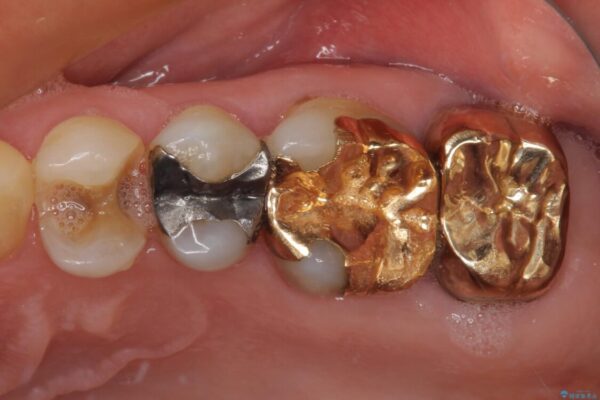

治療後

• 外れてしまった銀歯 セラミックインレーで自然な仕上がりに 治療後画像

正面から見える場所であったため、セラミックインレーで自然な口元にすることができました。